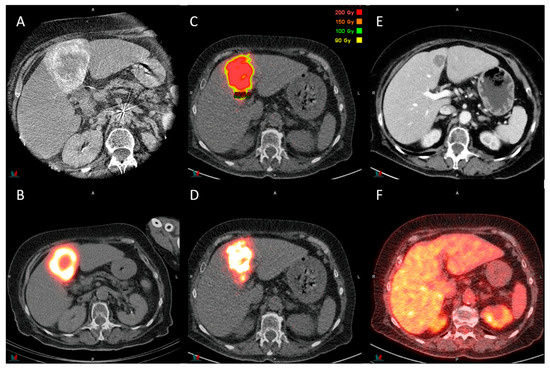

Image-guided therapies have transformed the landscape of liver tumor treatment, offering minimally invasive options with increased precision and improved patient outcomes. These therapies—ranging from ablation techniques such as microwave ablation and irreversible electroporation to vascular interventions like radioembolization with yttrium-90 microspheres, chemoembolization, portal vein embolization, and double vein embolization—are rapidly evolving with advances in imaging, technology, and interdisciplinary collaboration.